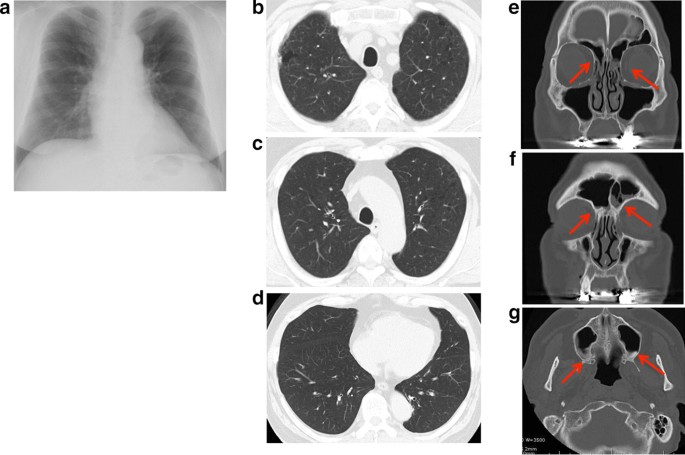

The patient experience his first bronchial asthma attack at 22 cycles of nivolumab treatment and was treated with a short course of corticosteroid burst therapy with 20 mg prednisolone along with inhalation therapy with budesonide/formoterol fumarate. This bronchial asthma attack was thought to be an adverse event associated with nivolumab; however, the patient continued the same dose of nivolumab treatment until 37 cycles because a good response against the kidney neuroendocrine carcinoma had been achieved. This clinical course is summarized in the Additional file 1: supplementary figure. Although nivolumab treatment had been discontinued until 37 cycles, the absolute eosinophil count remained high (26.6%, 1782.2 cells/μL) and his serum immunoglobulin E (IgE) levels were increased (924 IU/mL). Titers of anti-nuclear antibodies and anti-neutrophil cytoplasmic antibodies remained in the normal range. An IgE-radioallergosorbent test detected normal IgE levels, except against Japanese cedar and white cedar pollen. His fractional exhaled nitric oxide level was elevated to 107 ppb (normal range: 15–37 ppb). The patient had no history of allergy: however, all of his children had allergic bronchial asthma. He also showed dyspnea on exertion, developed sputum, and exhibited swelling and pain in his bilateral fingers. There were no other physical findings, including wheezing. Chest X-ray and computed tomography (CT) scanning detected a bilateral linear shadow which was not detected at his first visit to our hospital (Fig. 1a–d), and paranasal sinus CT scanning showed inflamed ethmoid, frontal, and maximal sinuses, indicating sinusitis (Fig. 1e–g). Although he had a normal respiratory function before initiating nivolumab treatment (FEV1.0 = 3.08 L, FEV1.0/FVC = 71.0%), his respiratory function test indicated an obstructive ventilation disorder (FEV1.0 = 1.63 L, FEV1.0/FVC = 50.6%). These results suggested that he had either eosinophilic pneumonia or EGPA. To confirm our hypothesis, we performed a bronchoscopy; the bronchoalveolar lavage fluid collected from the right B5 contained 40% lymphocytes and 3% eosinophils. Histopathological examination of a transbronchial lung biopsy sample from the right B8 showed small blood vessel hyperplasia with neutrophil infiltration and thickening of the alveolar septa with prominent eosinophil infiltration. Large numbers of red blood cells were observed on the lung tissue along with intra-alveolar bleeding (Fig. 2a, b), suggesting distinct alveolar hemorrhage with eosinophilic pneumonia. However hemosiderin-laden macrophages were not detected by Berlin blue staining, suggesting that the alveolar hemorrhage was an occasional event. Because he had experienced several bronchial asthma attacks and was already being treated with medication, the representative clinical findings needed for the bronchial asthma diagnosis were likely masked. To confirm the pathological findings of bronchial asthma, transbronchial mucosal biopsy was conducted. A bronchial mucosal lesion of the secondary carina also showed smooth muscle hyperplasia and thickening of the basement membrane with eosinophil infiltration (Fig. 2c). These findings suggested that the patient had bronchial asthma, eosinophilic pneumonia, and small vessel vasculitis. Finally, nerve conduction analysis showed that his right ulnar nerve conduction velocity was slightly decreased. There were no brain metastatic diseases, cervical spondylosis, or abnormalities related to rheumatoid arthritis. Although we could not definitively diagnose his neurological abnormalities, EGPA was thought to be one cause of the neuropathy. According to these findings with small vessel vasculitis, the patient was diagnosed with EGPA as per the American College of Rheumatology criteria for EGPA [5]. Distinct alveolar hemorrhage was not severe in the clinical setting and no heart involvement was detected; thus, treatment with 20 mg/day oral prednisolone was started. After 3 months, his bronchial asthma was improved, and bilateral infiltration had disappeared, as shown in Fig. 3. Steroid therapy was gradually tapered; during its discontinuation to less than 10 mg/day, a biweekly dose of mepolizumab (300 mg/day) was started to treat the EGPA. Currently, the patient is being treated with both nivolumab and mepolizumab, his peripheral eosinophilia has almost disappeared, and his respiratory function has improved (FEV1.0 = 2.94 L, FEV1.0/FVC = 71.2%), with paranasal sinus CT scanning showed normal findings (Fig. 3) after a year of treatment. He appears to be stable except for his neuropathy; to date, there have been no bronchial asthma attacks or CT scan abnormalities (Fig. 3).

Thoracic radiogram (a), CT scans of chest (b–d) and ethmoid sinus (e), frontal sinus (f) and maxillary sinus (g) after a year from initiation of treatment for EGPA. Chest radiogram (a) shows no any abnormal shadows. Thoracic CT scan of upper (b, c) and lower lobes (d) also does not show any ground-glass opacity. Each arrow in e–g indicates nasal mucosa thickening and fluid collection that was shown in e–g